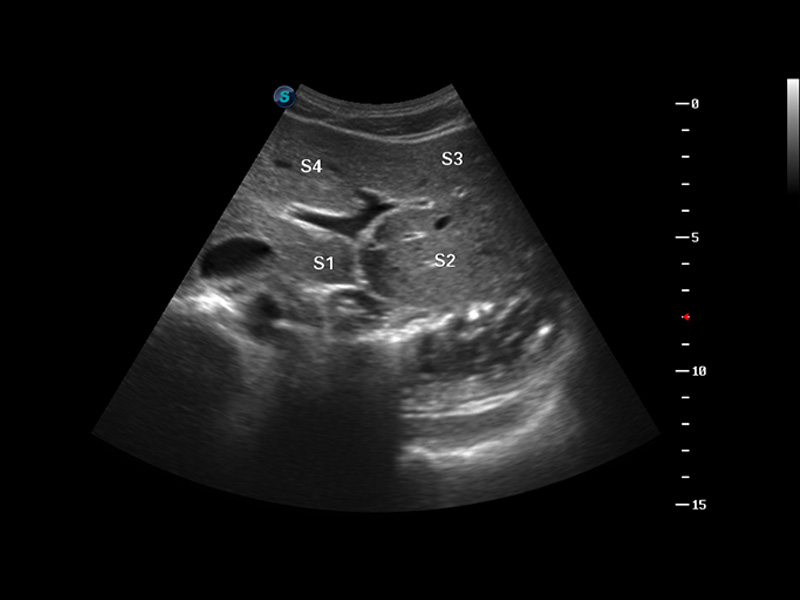

S8 EXP便攜式彩色多普勒超聲診斷儀是開立醫(yī)療研發(fā)的高端全身應(yīng)用型便攜彩超。高通道的VIS平臺(tái)融合可視化(Visual)、智能化(Intelligent)和人性化(Smart)的特點(diǎn),配以開立醫(yī)療自主研發(fā)生產(chǎn)的探頭大家族,使您能夠快速、準(zhǔn)確的獲得病人信息,提高工作效率的同時(shí)減輕疲勞。

成像技術(shù)

3D/4D成像